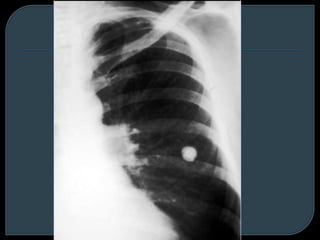

Granuloma +

adenopatía hiliar

calcificada

Hamartoma